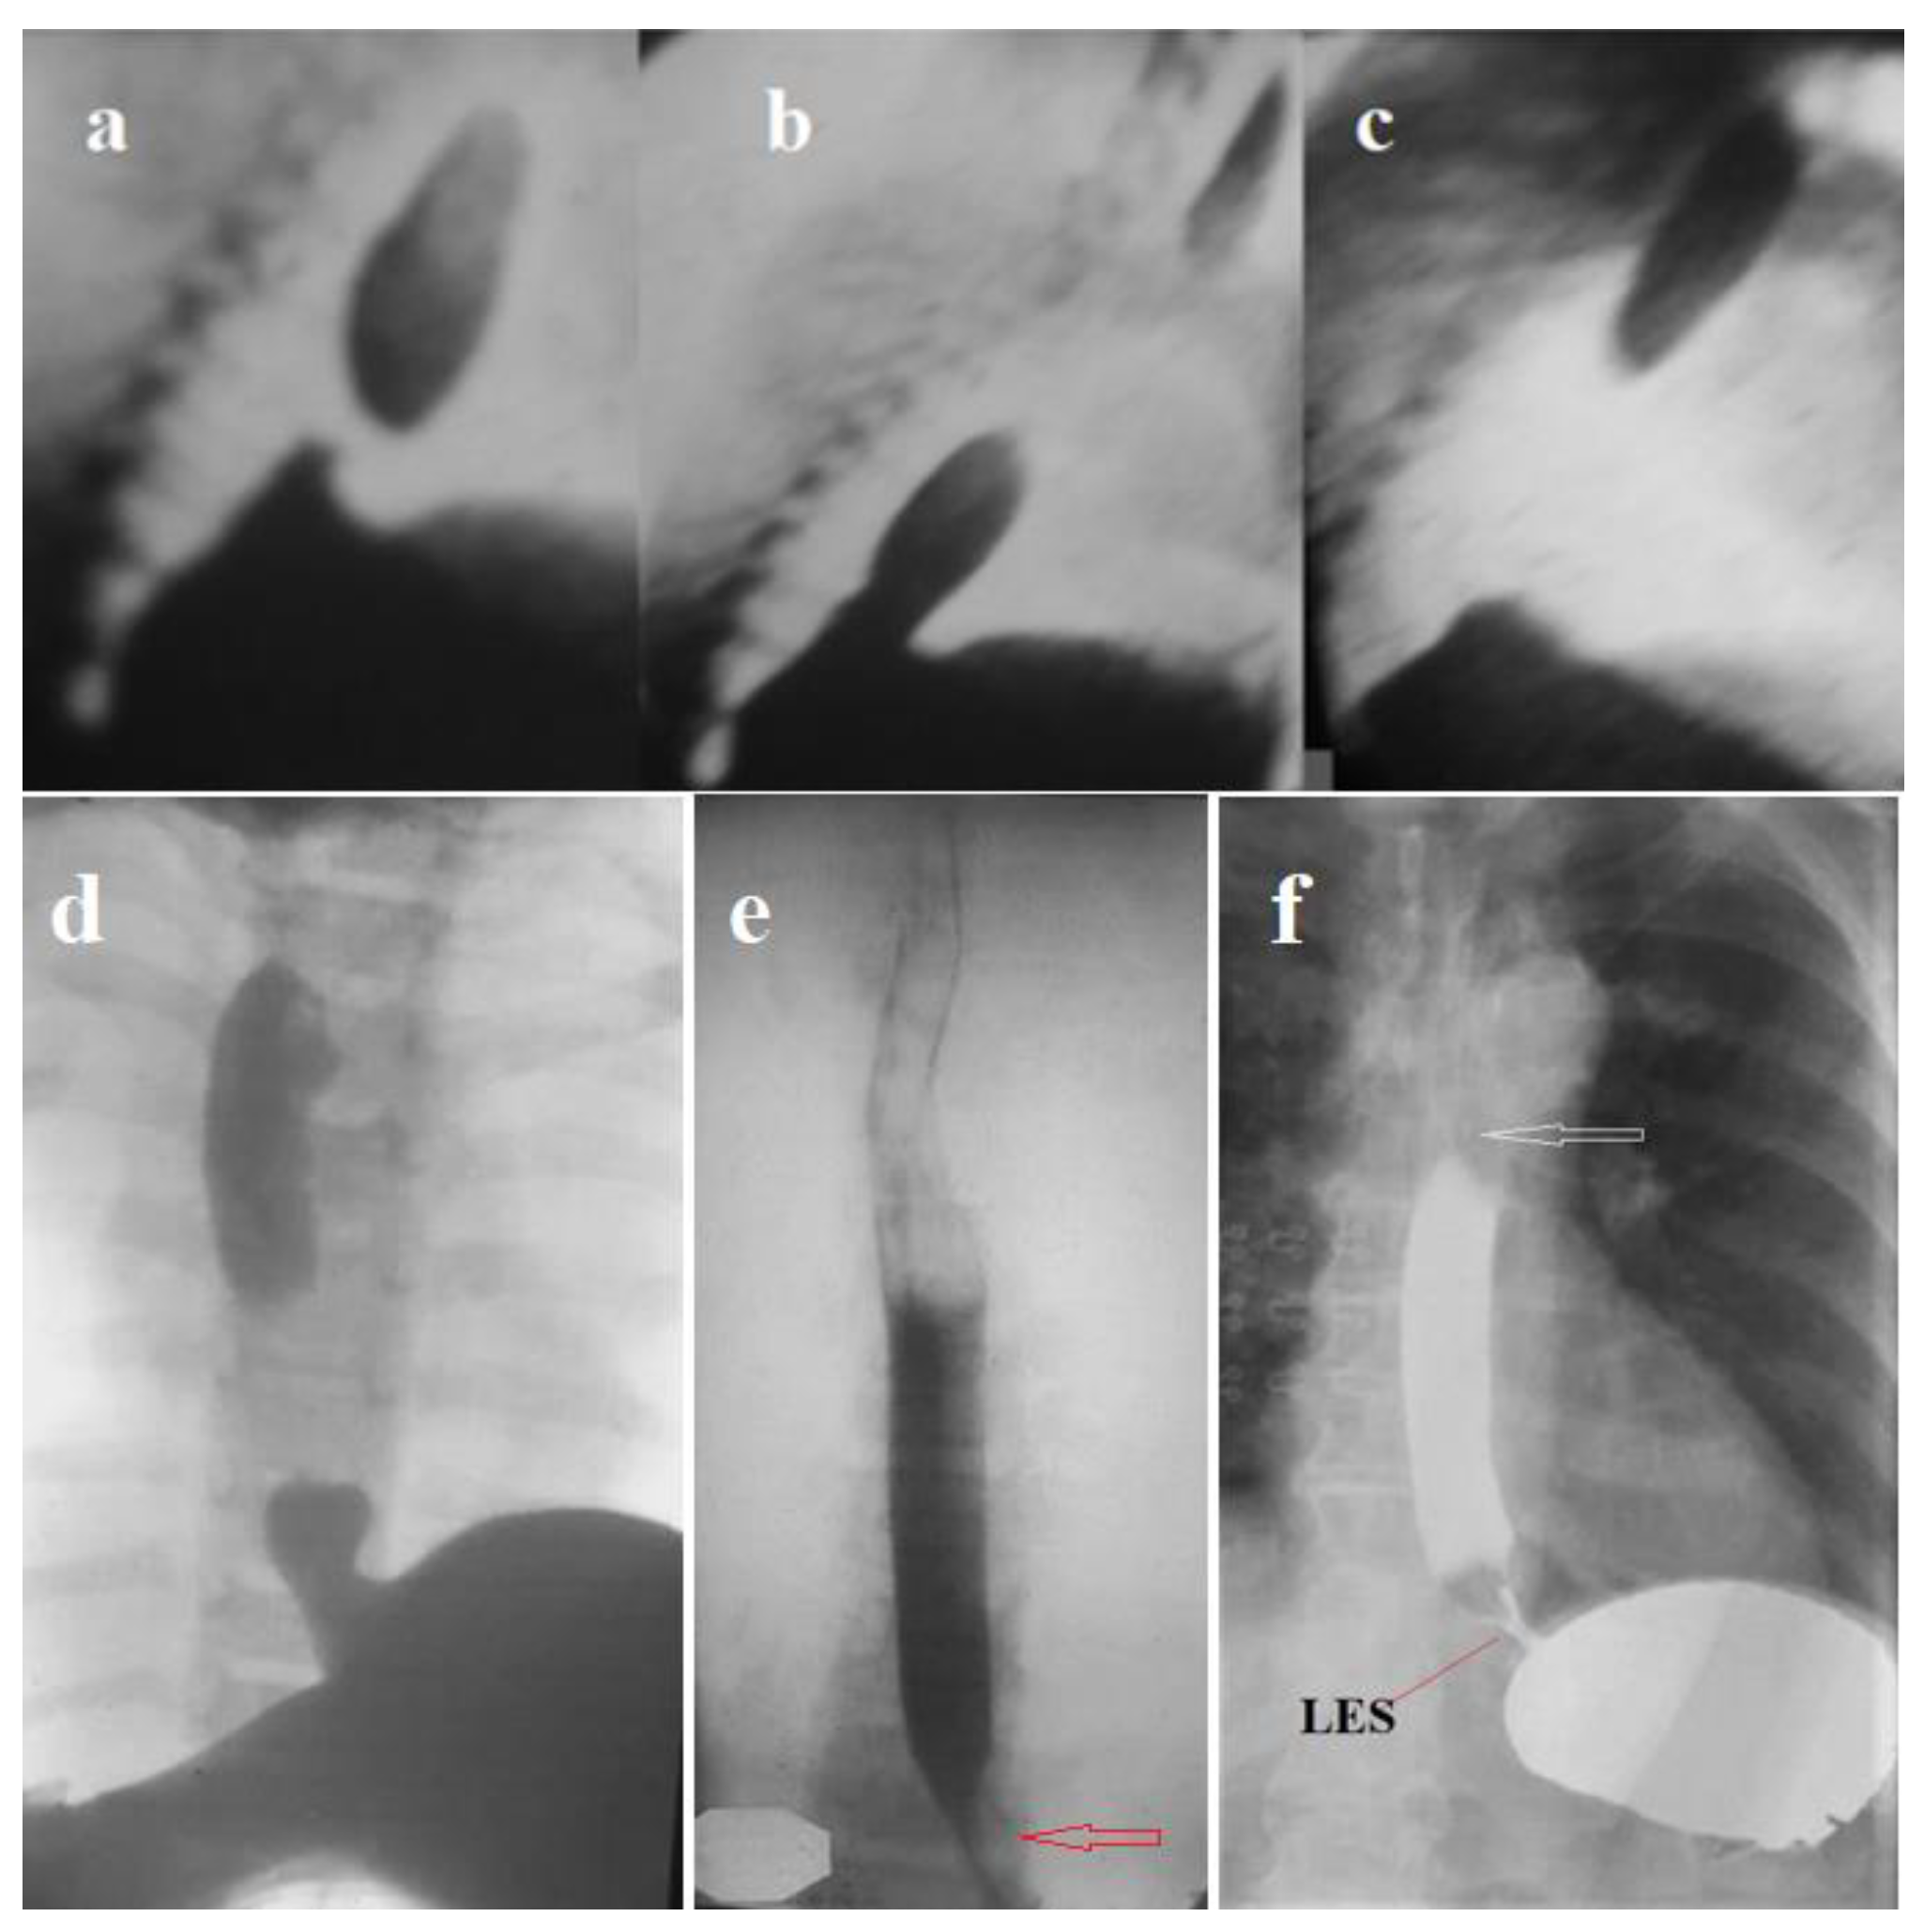

- I have proven the appearance of a functional sphincter in GERD. During eating thick foods, its contraction closes the proximal lumen of the ampulla, helping to create high pressure in the ampulla to inject the bolus into the stomach. It also contracts to prevent reflux above the ampulla. This proximal sphincter (PS) is 5–7 cm long [42]. Over time, it turns into a fibrous ring of different diameters. In some patients, PS turns into a narrow fibrous ring that impairs passage along the esophagus. This is the so-called Schatzki ring [42,50].

- I have proven the appearance of another functional sphincter, which is often observed in non-esophageal manifestations of GERD. This sphincter is in the area of the aortic narrowing of the esophagus. That’s why I called it the aortic sphincter of the esophagus (ASE). Its contraction prevents reflux of the chyme into the upper esophagus and pharynx.